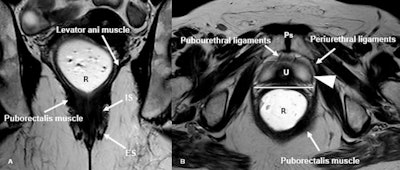

Normal female pelvic floor anatomy. (A): Coronal T2-weighted MR defecography highlighting the levator ani complex and both internal and external anal sphincters. (B) Axial T2-weighted image depicts the urethral support structures: periurethral ligaments from the puborectalis, paraurethral ligaments (arrowheads) from the urethral wall, and pubourethral ligaments from the pubic bone to the urethra. The vagina (V) shows a typical H-shaped configuration. Ps = pubic symphysis, R = rectum, U = urethra, IS: internal anal sphincter, ES: external anal sphincter.Pugliesi et al; EJR